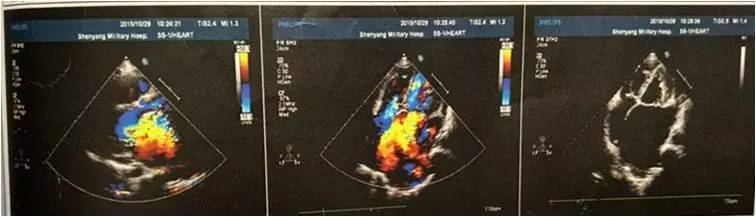

检查日期2015-10-29

左房内径(mm ):92mm

左室舒张末期内径(mm):76mm

右室内径(mm):30 mm

LVEF:47%

超声提示二尖瓣后叶脱垂并重度关闭不全,二尖瓣后叶部分腱索呈“梿枷样”改变,提示二尖瓣后叶部分腱索断裂,三尖瓣中重度关闭不全,肺动脉高压(跨三尖瓣压差 53mmHg),心包积液少量。